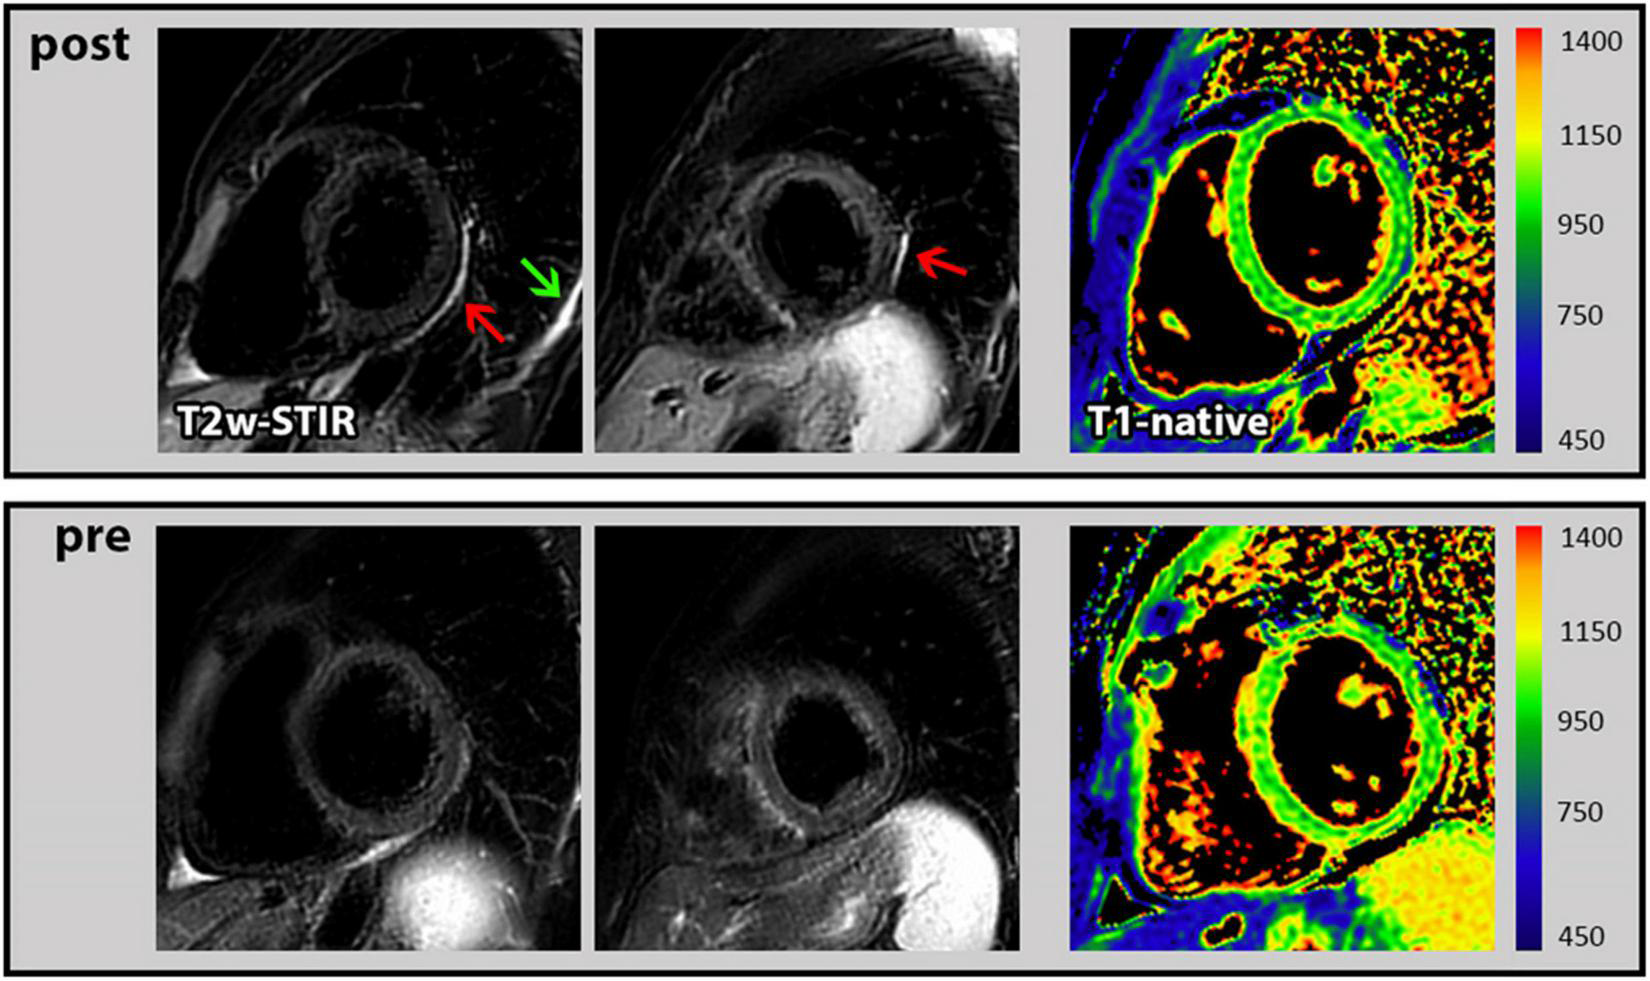

In general, the assessment of both functional as well as structural CMR parameters showed highly consistent and reproducible values when the respective CMR parameters measured before and after the booster vaccination were compared. In particular, there was no change in biventricular function and volumes, in global longitudinal strain and in myocardial mass (Table 2). Moreover, the global native T1- and T2-mapping values remained unchanged (988 vs. 983 ms in T1 and each 50 ms in T2). There was one female who demonstrated a new “pericardial” T2-STIR-weighted hyperintensity in the basal to midventricular inferolateral pericardium and also a new pleural effusion (Figure 1). In the absence of any symptoms or signs of other diseases, we interpreted these findings as a vaccination-associated form of very mild pericardial inflammation. There was no known clinical characteristic or laboratory parameter that could provide a predisposition to pericarditis in this case.

Figure 1. Cardiac magnetic resonance (CMR) images of pericarditis. First row: T2-STIR-weighted short-axis images with the occurrence of pericardial hyperintensity as indication for edema/mild pericardial inflammation (red arrow) and a new pleural effusion (green arrow) following the 3rd COVID-19 vaccination. In addition, corresponding T1 mapping without signs of myocardial impairment. Second row: Corresponding images at baseline (prior to 3rd COVID-19 vaccination) from the same subject without any pathological findings.